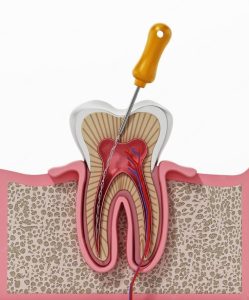

روند درمان عصب کشی به طور کلی شامل مراحل زیر است:

تشخیص اولیه:

قبل از هر چیز، دندانپزشک نیاز دارد تا دندان را بررسی کند و علت درد یا آسیب را شناسایی نماید. این مرحله شامل بررسی بالینی و همچنین استفاده از رادیوگرافی دندان است تا وضعیت عصب و بافتهای داخلی دندان به دقت مورد ارزیابی قرار گیرد.

بیحسی و آمادهسازی دندان

برای این که بیمار اذیت نشود از بیحسی سطحی استفاده میشود. این به این معنی است که فقط ناحیه درمان بیحس میشود و بیمار در طول درمان درد نخواهد داشت. سپس دندانپزشک به کمک ابزارهای دقیق، حفره دندان را باز میکند تا به بافت عصبی آسیبدیده دسترسی پیدا کند.

پاکسازی کانالهای ریشه

در این مرحله، دندانپزشک با استفاده از ابزارهای خاص، کانالهای ریشه را از عصبها و بافتهای آسیبدیده و عفونی پاک میکند. این فرایند بهدقت انجام میشود تا هیچگونه باقیماندهای در داخل کانالها باقی نماند.

پر کردن و مهر و موم کانالها

پس از پاکسازی، کانالهای ریشه با مواد خاصی پر میشوند تا از نفوذ باکتریها و عفونتهای احتمالی در آینده جلوگیری شود. این مواد معمولاً از نوع گوتاپرکا هستند که محکم و مقاوم در برابر عفونت هستند.

پر کردن دندان و ترمیم نهایی

در نهایت، برای بازسازی دندان، دندانپزشک با استفاده از مواد پرکننده مناسب دندان را ترمیم میکند. در برخی موارد، ممکن است دندان نیاز به تاج دندانی داشته باشد تا استحکام آن افزایش یابد و دندان بهطور کامل بازسازی شود.